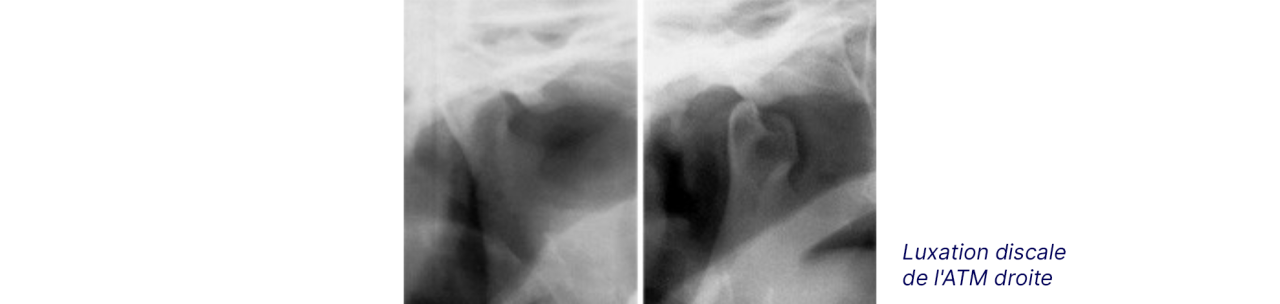

Les troubles de l’articulation temporo-mandibulaire (ATM)

Chez certains patients, les articulations des mâchoires peuvent être très sensibles aux malocclusions et au rétablissement d’une occlusion correcte par l’orthodontie. Ces patients peuvent souffrir d’une ouverture buccale limitée, de crépitements, claquements, craquements ou douleurs aux ATM. Cependant, ces signes sont dans la majorité des cas signalés chez des patients n’ayant pas eu recours à un traitement orthodontique.

Les corrections de malpositions dentaires par l’orthodontie peuvent améliorer le fonctionnement des ATM sans toutefois garantir l’amélioration ou l’élimination des symptômes. Des symptômes peuvent même apparaitre sans que l’orthodontie en soit la cause.

Radiographies qui présentent le risque de luxation.